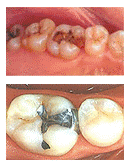

아말감 치료

아말감은 은과 주석의 합금에 수은을 섞어서 굳게 하는 재료로 전통적으로 가장 많이 쓰인 재료입니다. 보통 은으로 때웠다고 할 때나, 검은색 재료로 때웠다고 할 때는 이것을 말하는 것입니다. 의료보험 혜택이 있어 비용이 저렴하고 진료 방법이 간단하며 너무 크지 않은 대부분의 충치 치료를 할때 많이 사용했으나 보기에 좋지 못하고 수은의 사용 때문에 찬반의 논란이 많습니다.